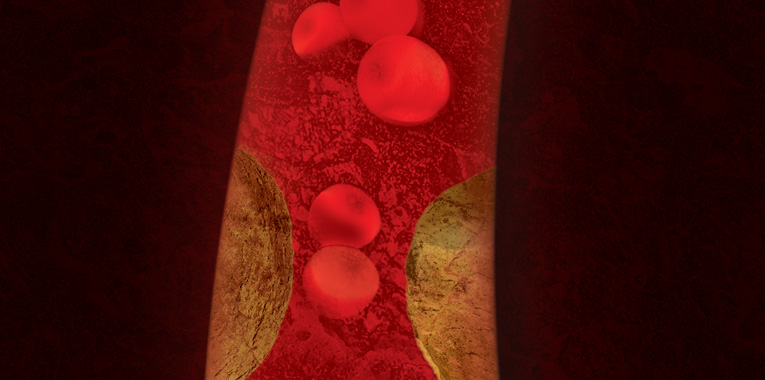

Essa doença ataca as artérias, geralmente fazendo com que placas de gordura se acumulem, diminuindo o calibre e consequentemente a passagem do sangue no local. E a doença é séria: está provado cientificamente que pacientes com problemas de circulação do sangue têm maior risco de ter problemas graves do coração, aumentando inclusive o risco de morte.

O problema atinge todas as artérias do pescoço, principalmente as das pernas, do rim e da barriga – a conhecida aorta. Nela, além da obstrução, o que comumente ocorre é a dilatação, chamada de aneurisma de aorta, que nada mais é que uma fraqueza da parede do vaso sanguíneo e quando rompe é fatal, devido à grande perda de sangue.

Já a obstrução da artéria renal, por exemplo, causada pelo acúmulo de cálcio e gordura, pode causar hipertensão arterial de difícil controle e sobrecarrega as artérias do coração, trazendo graves riscos.

Para o especialista, é possível controlar a doença na maioria dos pacientes. Além do tratamento medicamentoso, os procedimentos da radiologia intervencionista têm trazido benefícios comprovados cientificamente. Na intervenção é feita uma angioplastia para dilatar as artérias e implantado o stent (pequena prótese metálica tubular), que fica por dentro da parede da artéria, desobstruindo-a e estabilizando o fluxo sanguíneo. Minimamente invasivo, este procedimento é realizado através de uma pequena incisão na virilha.

Em relação ao cérebro, as estatísticas médicas apontam a falta de circulação cerebral como sendo a maior causa de sequelas e morte de pacientes no mundo moderno. A obstrução das artérias carótidas também pode ser evitada com a angioplastia, que apresenta baixos índices de complicações (em torno de 1 a 2%) devido ao avanço dos materiais que hoje são utilizados.

Um desses materiais é filtro de proteção, que faz com que o paciente esteja protegido de eventuais deslocamentos de placas para a circulação do cérebro durante o procedimento de angioplastia. Este filtro funciona com um pequeno coador que deixa apenas sangue passar, barrando eventuais fragmentos da placa de gordura calcificada.